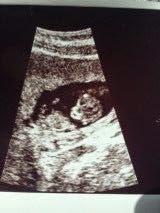

Since Tuesday, I’ve been a mess. The emotional toll of all this, combined with my awful nausea and vomiting that seems to be getting worse rather than better, has just about done me in. I had a mini-breakdown at my OB appointment this morning, and realized I’ve been disconnected from this baby- all I’ve been focusing on is how awful I feel. I don’t think I was supposed to have an ultrasound today, but after I tearfully told her everything that was going on with me and Grayson, my doctor took me into the ultrasound room and said, “Let’s look at your baby.” I’m so grateful she did. I saw my baby that 4 weeks ago was just a blinking dot on the screen and now actually looks like a baby. He or she was wiggling and moving like crazy, had a perfect heartbeat, and was measuring once again to the day- 11 weeks, 2 days. Life truly is a miracle, and never gets old, even the third time around.